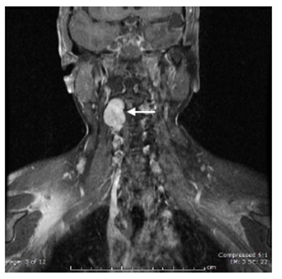

A giant meningioma of the right olfactory groove measuring 7cm x 6cm x 5.2cm (Figure 1); a left giant lesser sphenoid wing meningioma measuring 7cm x 6.5cm x 4.8cm (Figure 2); both tumors producing significant edema and brain herniation (Figures 1&2). Small bilateral vestibular schwannomas, two small falx meningiomas and a cervical schwannoma from C1 to C3 (Figure 3).

Figure 3 T1 Gadoline enhanced coronal MRI shows the cervical C2-C3 Schwannoma (white arrow).